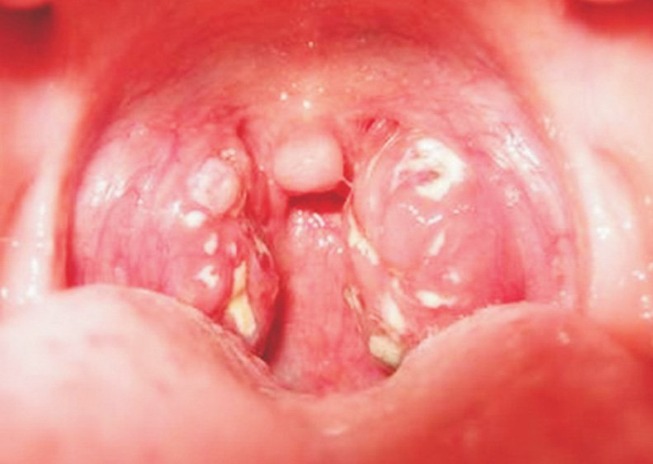

Đến đêm 30/6, bệnh nhân đến Trung tâm Y tế huyện Kỳ Sơn với tình trạng mệt mỏi, da, niêm mạc kém hồng, sốt 37,8 độ C, ho, đau họng, khàn tiếng, sưng vùng cổ phải, nuốt đau, nổi hạch góc hàm 2 bên, amydal to có dịch mủ, có giả mạc trắng bám amydal và lưỡi gà, dễ bóc tách. Bệnh nhân được chẩn đoán mắc bệnh bạch hầu.

Bệnh bạch hầu là một bệnh truyền nhiễm nguy hiểm do vi khuẩn Corynebacterium diphtheriae gây ra. Vi khuẩn này thường tấn công niêm mạc mũi và họng, tạo ra màng màu xám hoặc trắng trên cổ họng, gây khó thở, khó nuốt. Bệnh bạch hầu cũng có thể lây lan sang da và gây ra các tổn thương.

- Có màng xám hoặc trắng trên cổ họng